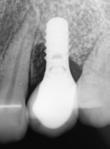

Der ses anterior trangstilling i begge kæber og overerupterede 1+1 og 2,1-1,2, hvilket resulterer i dybt bid med 2- tæt på ganepåbidning. Der er normale sidetandsrelationer, men der ses 5 mm horisontalt overbid (HOB) og 7 mm vertikalt

overbid (VOB). Papillen mellem 1+1 er betydeligt reduceret pga. fæstetab, og de mesialt kippede 1+1 har resulteret i en ”dark triangle”. Den facioorale funktion er for nuværende i.a. Panoramarøntgen (Fig. 1, I) viser marginalt knogletab i begge kæber og fravær af 8,7+7,8 og 8,7-8.

Der planlægges alignerbehandling af begge kæber med intrusion af 1+1 og 2,1-1,2, nivellering af trangstilling UK med interproksimal reduktion (IPR) (Fig. 2 A, B) og senere IPR OK for reduktion af dark triangles mellem incisiverne efter nivellering. Patienten instrueres i at benytte alignere 20-22 timer/ dag med alignerskift hver 7. dag, og patienten ses hver 3.-8. uge under forløbet. Den første alignerserie består af 16 alignere for nivellering OK/UK og IPR i UK (Fig. 2). Efter denne serie planlægges IPR mellem incisiverne i OK for reduktion af dark triangles (Fig. 3) samt yderligere intrusion af OK og UK-fronten i 12 refinement-alignere. Patienten udviser god kooperation og er meget tilfreds med alignerapparaturet, som er mindre synligt end det faste apparatur (Fig. 4).